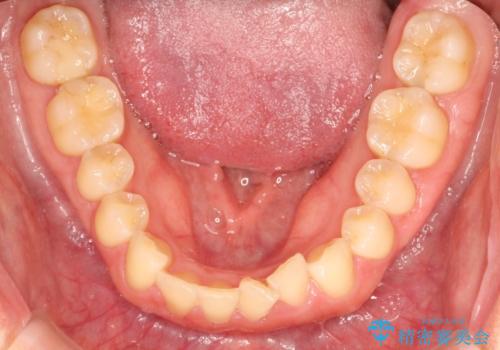

- 前歯の歯並びが気になるとのことで来院されました。

右上の1番目の歯が内側に入り込んでしまっており、その歯がの先端がすり減ってしまっていました。

インビザラインによる矯正治療で前歯の歯並びを改善し、セラミッククラウン装着により歯の形態の回復をする計画としました。

矯正とセラミックを併用することで、より完成度の高い状態に仕上げることができました。